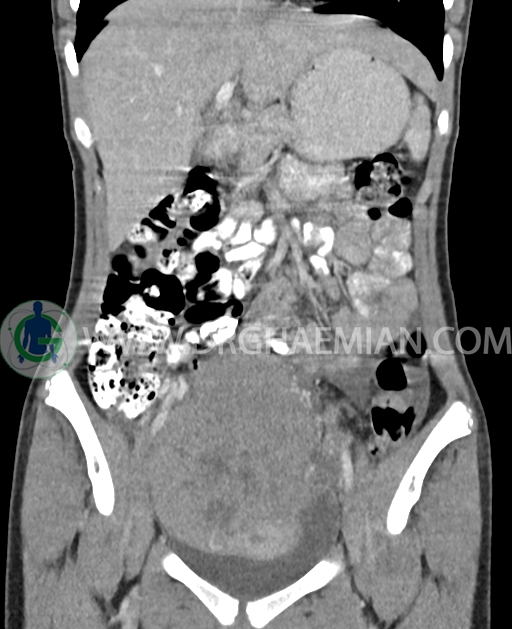

سی تی اسکن شکم و لگن از تشعشعات برای ایجاد تصاویر عرضی مقطعی از نایحه شکم و بین استخوان های لگن استفاده می کند. در این کیس تومور سلول زایا به ابعاد mm 125 x 112 x 80 دیده می شود.

در سی تی اسکن اسپیرال شکم و لگن با کنتراست خوراکی و وریدی (مولتی دیدکتور 16 با مقاطع ظریف و بازسازی های ساژیتال و کرونال) :

توده هیپردنس لوبوله بزرگ به ابعاد 125x112x80mm حاوی نواحی سیستیک داخلی و enhancement قابل توجه پریفرال همراه با آسیت متوسط در فضای شکم و لگن با احتمال بیشتر با منشا از تخمدان راست، درون لگن دیده می شود که در درجه اول مطرح کننده germ cell tumor می باشد .